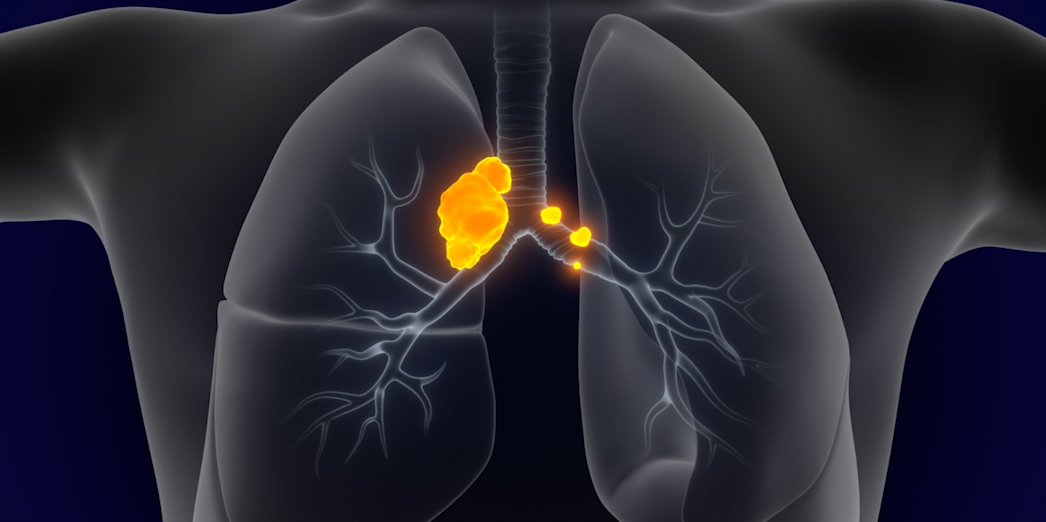

Learn about expanding options to delay relapse after induction.

1L TREATMENT- Rudin CM, Brambilla E, Faivre-Finn C, Sage J. Small-cell lung cancer. Nat Rev Dis Primers. 2021;7(1):3. doi:10.1038/s41572-020-00235-0

- Byers LA, Rudin CM. Small cell lung cancer: where do we go from here? Cancer. 2015;121(5):664-672.

- Huber RM, Tufman A. Update on small cell lung cancer management. Breathe. 2012;8(4):314-330.

- Small cell lung cancer stages. American Cancer Society. https://www.cancer.org/cancer/lung-cancer/detection-diagnosis-staging/staging-sclc.html. Accessed March 25, 2025.